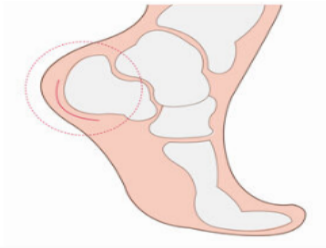

“經(jīng)X光、磁共振等詳細(xì)檢查,提示患者雙側(cè)跟骨結(jié)節(jié)增生、跟腱有變性,雙側(cè)跟骨結(jié)節(jié)區(qū)域及跟腱止點(diǎn)表現(xiàn):組織充血、水腫,結(jié)合病情及查體,考慮跟骨骨性突起畸形,經(jīng)診斷,為Haglund綜合癥(止點(diǎn)性跟腱炎、跟骨后上突增生與跟腱滑囊炎的統(tǒng)稱)?!崩畋蛑魅伪硎荆摬“Y主要表現(xiàn)為跟腱止點(diǎn)部位疼痛不適,運(yùn)動時疼痛加劇;或者清晨起床后出現(xiàn)疼痛,漸進(jìn)性病程發(fā)展,后期疼痛加重,影響生活質(zhì)量。

跟痛癥是以足跟部疼痛而命名的疾病,是指足跟部周圍組織不同程度的慢性勞損所引起以疼痛及行走困難為主癥狀,常伴有跟骨結(jié)節(jié)部骨刺形成。

具體表現(xiàn):1.腳后跟外觀上可見少許凸起;2.局部有壓痛;3.時有腳后部及底部疼痛發(fā)作,行走時或站立時疼痛。如果你或者你的家人有過類似的經(jīng)歷,那很可能就是這個病了。